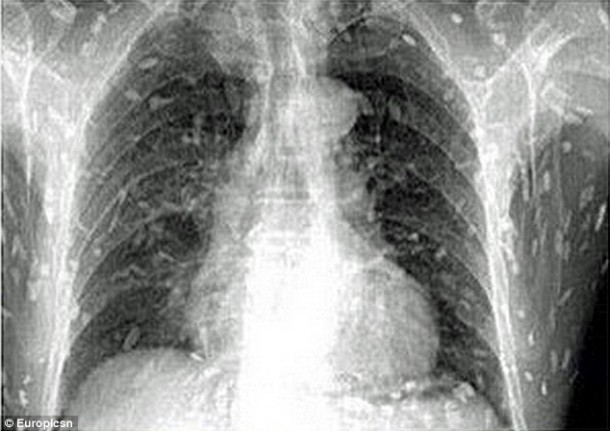

Sur place, le médecin lui fait passer des radiographies pour identifier la cause de son mal-être. Les radiographies révèlent que l’homme a des larves de ténia dans tout le corps. Le Dr Yin, a indiqué que l’homme « avait probablement mangé du poisson cru contaminé par des oeufs ». C’est à cela que l’homme doit son infection parasitaire. Si son cas n’avait pas été traité rapidement, l’homme aurait pu mourir. En effet, lorsque l’infection atteint le cerveau, cela peut se révéler mortel.